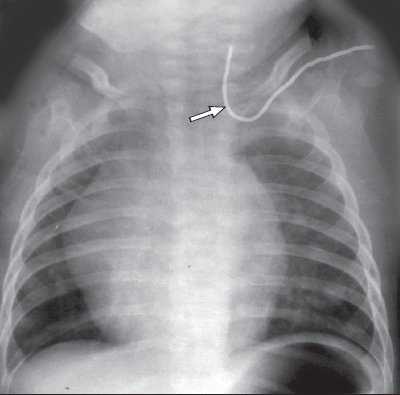

Одной из проблем при катетеризации центральных вен является корректная позиция центрального венозного катетера, при которой его конец должен находиться в полости верхней полой вены над правым предсердием. По данным отечественных и зарубежных исследователей, некорректная позиция центрального венозного катетера против тока крови встречается в 0,5-18% случаев (в 5-18% при катетеризации v. subclavia и в 0,5-5% при катетеризации v. jugularis interna). Наиболее частым вариантом некорректной позиции является расположение катетера в полости внутренней яремной вены при катетеризации одноименной подключичной вены (рис. 6). В настоящее время существует несколько методов верификации позиции центрального венозного катетера: рентгено-контроль, ЭКГ-контроль; одним из них на практике становится УЗИ для уточнения положения центрального венозного катетера (рис. 7, 8).

Рис. 6. Рентгенография. Некорректная позиция центрального венозного катетера, установленного через подключичную вену (катетер расположен против тока крови во внутренней яремной вене).

Рентгенологический контроль положения центрального катетера

После катетеризации внутренней яремной или подключичной вены необходимо произвести рентгенографию органов грудной клетки для подтверждения правильного расположения катетера и исключения пневмоторакса. Если больному проводится ИВЛ – рентгенография проводится сразу после катетеризации. При самостоятельном дыхании больного – через 3-4 часа. При признаках гемоторакса, пневмоторакса – рентгенография проводится немедленно.

Определение правильного положения дистального конца катетера на ретгенограмме

На рентгенограмме грудной клетки в передней проекции у взрослых конец катетера должен располагаться не более чем на 2 см ниже линии, соединяющей нижние концы ключицы. Эта линия разделяет верхнюю полую вену на два участка, расположенных ниже верхней границы перикарда и выше нее. Если катетер вводят в нижнюю полую вену, его конец должен располагаться ниже уровня диафрагмы.